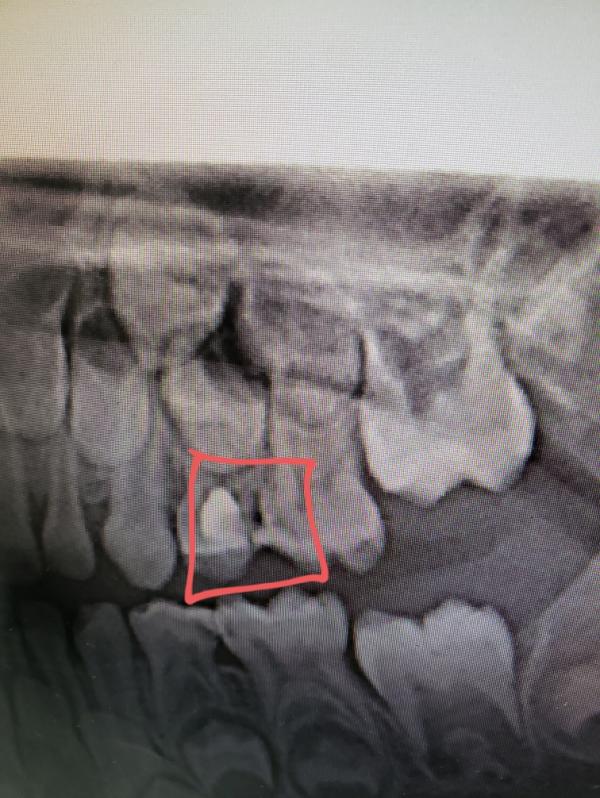

Девочки, кто обращался или планирует в стоматологию "Добрый крокодил" , в Перово. Возможно это нам не повезло, но вот на фото видно как сделали зуб ребёнку 2 месяца назад, причём это переделанная ими же работа, так как пломба выпала через месяц после первого лечения .

Когда обратились в др клинику уже по другому зубу, нам показали работу предыдущего стоматолога, на снимке с фотоаппарата вообще видно кариес. В итоге, если суммарно в двух клиниках, лечение зуба обошлось в почти 20 тысяч.

@nasemka пульпит лечили, и вот ту область что я обвела , белое - это пломба , а там где рядом затемнение это кариес, тоесть не всю область запломбировали или же плохо прочистили канал и зуб стал разрушаться